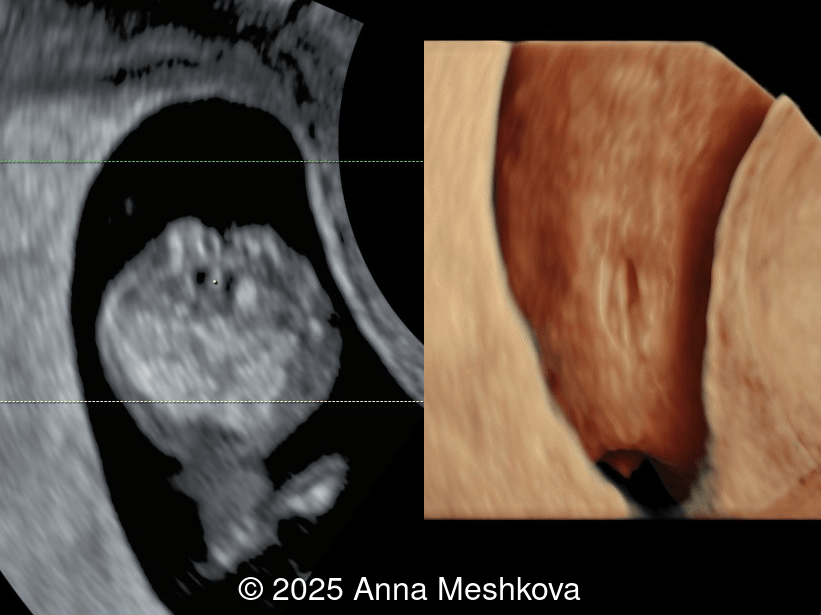

• Image 1:  Transverse section of the brain at the level of choroids. Subtle supporting sign of relatively large choroid plexuses and low surrounding cerebrospinal fluid known as the "dry brain" sign.

3D reconstruction of the spinal defect in the lumbosacral region at 13 weeks gestation

Image 1 3D reconstruction of the spinal defect in the lumbosacral region at 13 weeks gestation

Image 2 3D reconstruction of the spinal defect in the lumbosacral region at 13 weeks gestation